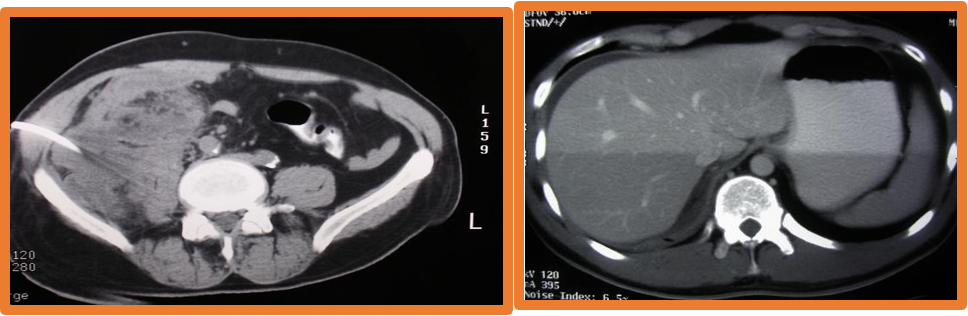

• Imaging:, AXR, Ultrasound, CT scan-most helpful